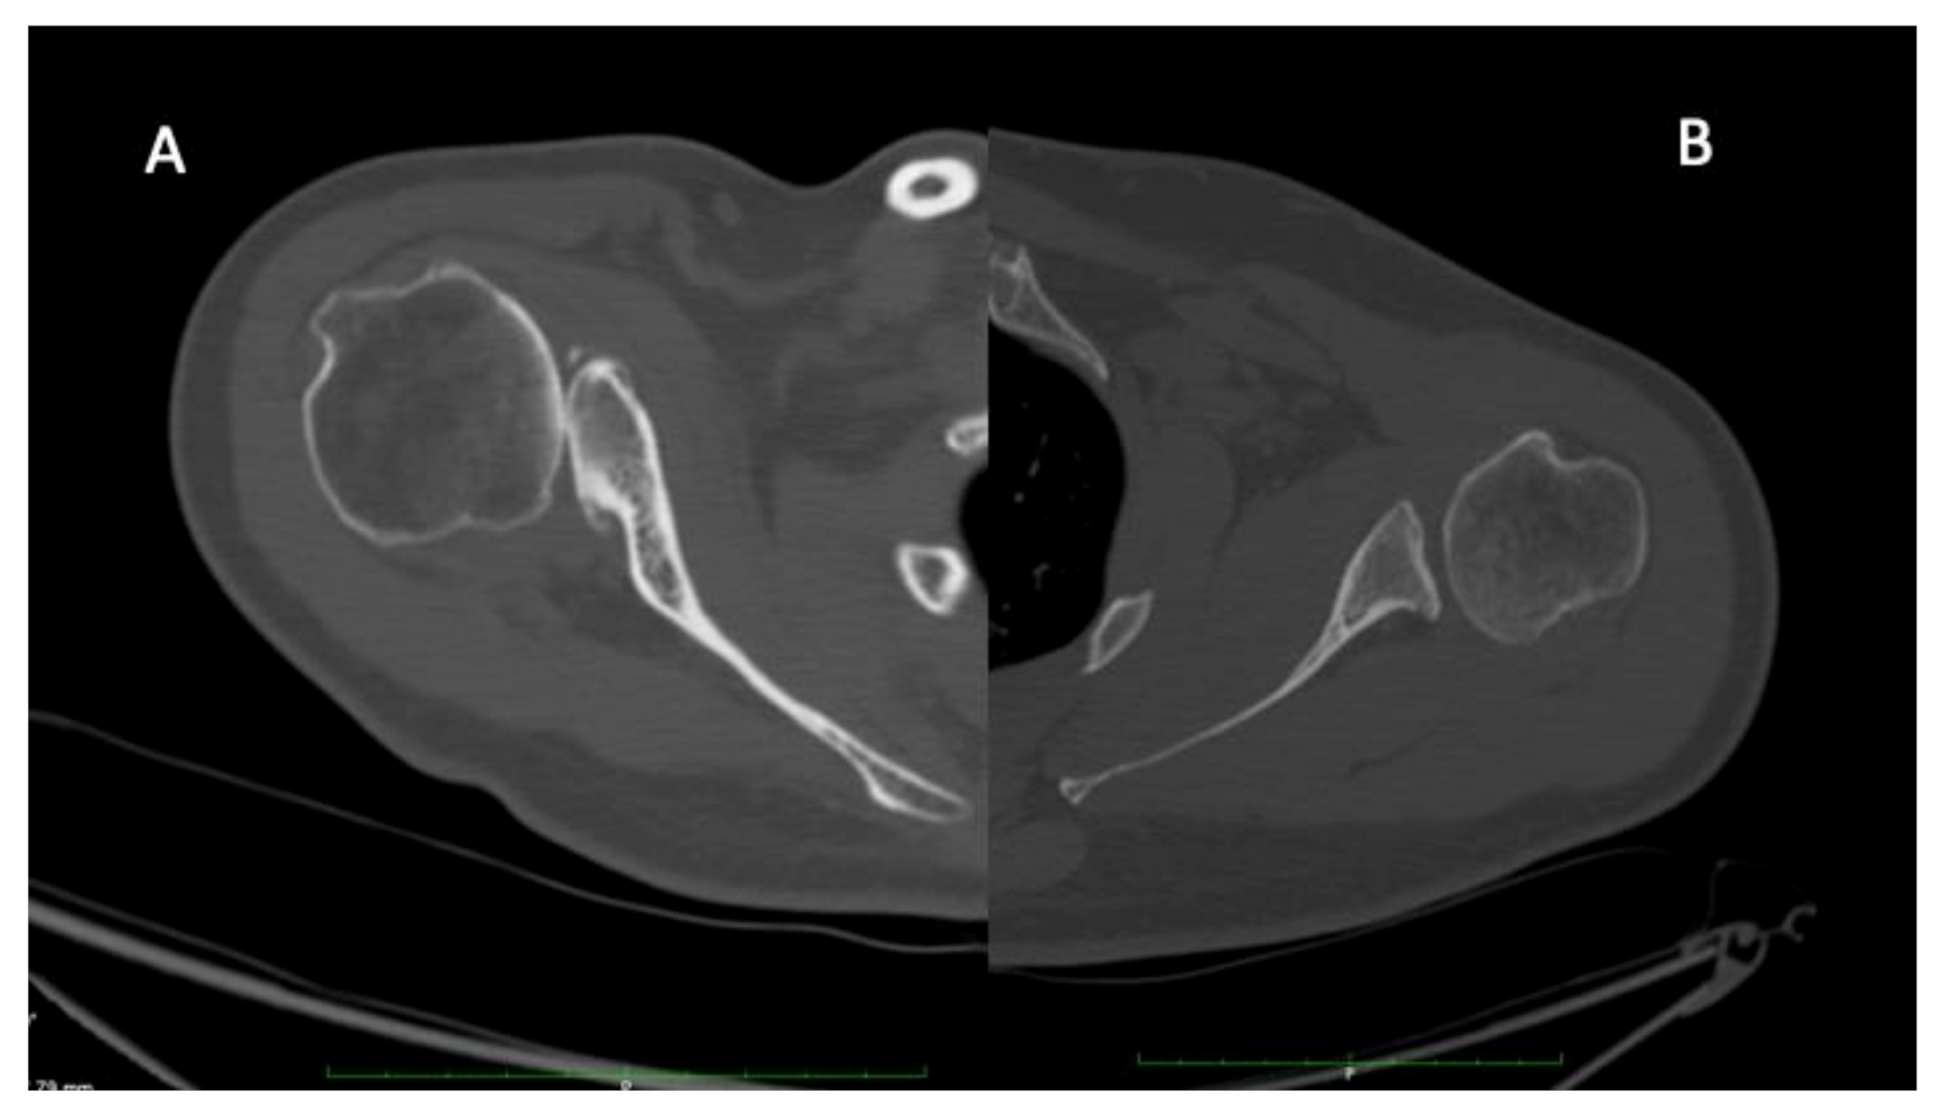

Figure 1.

Illustration of C (A) and B (B) glenoids. C glenoid observed in severe neurological lesion are characterized by a retroversion above 25 degrees, a humeral head subluxation above 80%, a rounded posterior rim, a “lazy J” sign and a hypoplastic neck. On the other hand, B glenoid are characterized by a retroversion above 15 degrees, a humeral head subluxation above 60%, a concave glenoid, osteophytes, a sharp posterior rim and a normal glenoid neck.

Forces asymmetry created in the glenohumeral joint, as seen in OBPP, affects joint development and lead to glenoid deformity [123]. There is a widespread opinion that undergrowth of the glenohumeral joint in OBPP develops gradually over time, as a consequence of an internal rotation contracture and muscular imbalance [123]. With severe lesions, there might be an increasing posterior displacement of the humeral head with development of a glenoid dysplasia (C glenoid, Figure 3A), whereas in subclinical impairment, a milder deformity (B glenoid, Figure 3B) might develop over decades.